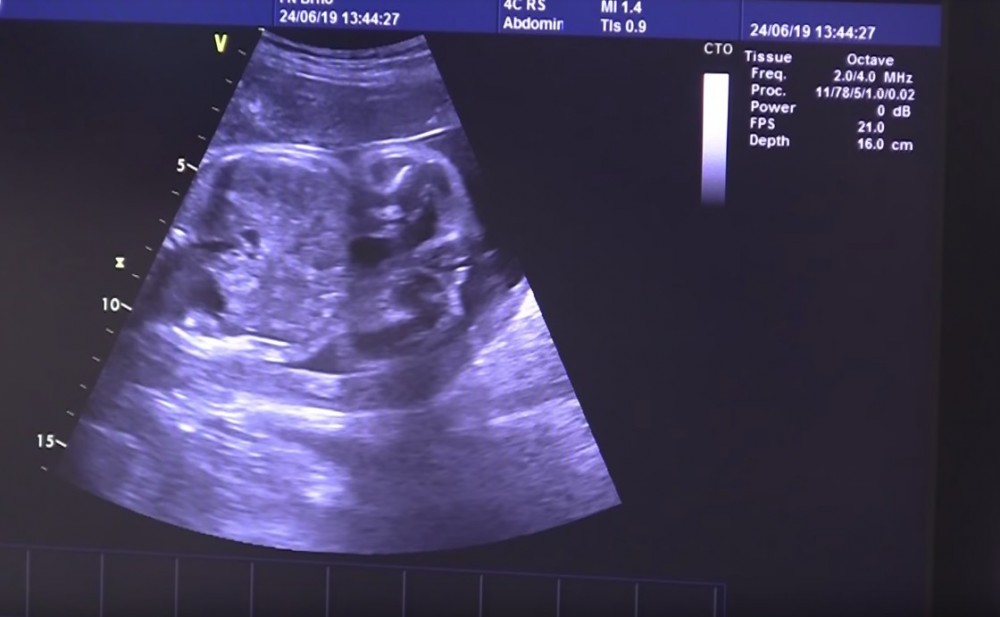

婦科委員會確定仍在媽媽肚中的嬰兒由6月24日的980克,升至7月中的1.5公斤。雖然胎兒有成長,但出現了4種具傳染性的併發症,需要使用抗生素。根據醫院的資料,全世界只有20宗類似個案,而這個個案更因媽媽的生命被維持了117天,以及嬰兒的成熟程度,成為最特別的案例。

幸運地,在8月15日,醫護人員為腦死的媽媽,剖腹產下一名2.13公斤,42厘米的女嬰。根據外國媒體《Global News》"Baby born 117 days after stroke leaves Czech mother brain-dead"一文,這名腦死媽媽,之後在丈夫和其他家人的陪伴下,醫護人員停了維持生命機器,結束這名偉大而堅強的媽媽的生命。